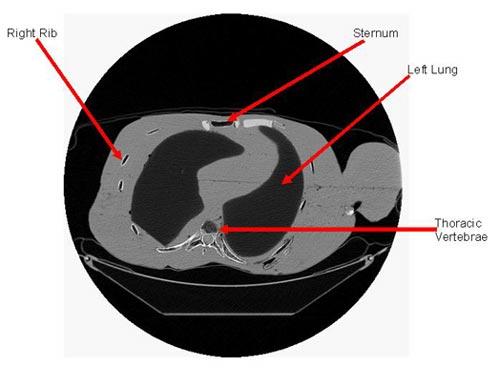

Dr. Wes Bolch’s Advanced Laboratory for RAdiation Dosimetry Studies (ALRADS) at the University of Florida is developing a suite of skeletal dosimetric phantoms for nuclear medicine patients aged from infancy to young adulthood. These are based on computer tomographic scan (CT-Scan) images taken post mortem. The ALRADS researchers have developed mathematical methods and software codes to render a series of two-dimensional CT-Scan image files into a three-dimensional voxel model of the whole body, including the trabecular and cortical bone structure of all parts of the skeleton. Among other activities, Dr. Bolch is contributing these ‘virtual phantom’ models to the ongoing work of the International Commission on Radiological Protection’s (ICRP’s) Task Group on Internal Dosimetry (INDOS). The three-dimensional modeling techniques developed by ALRADS are directly applicable to USTUR’s case studies – of elderly donors.